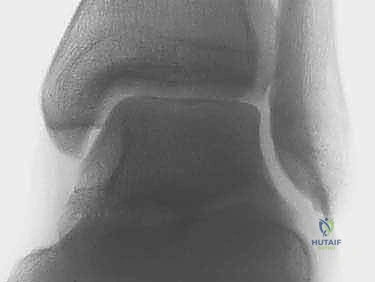

لفهم أهمية عملية تثبيت مفصل الكاحل بالمنظار، يجب أولاً إلقاء نظرة على التشريح المعقد لهذا المفصل الحيوي. مفصل الكاحل الأساسي، المعروف طبياً باسم المفصل الظنبوبي الرصغي (Tibiotalar Joint)، هو مفصل مفصلي (Hinge Joint) يتكون من التقاء ثلاثة عظام رئيسية:

1. عظمة الظنبوب (Tibia): وهي عظمة الساق الكبرى التي تشكل الجزء الداخلي والعلوي من الكاحل.

2. عظمة الشظية (Fibula): وهي عظمة الساق الصغرى التي تشكل الجزء الخارجي من الكاحل.

3. عظمة الكعب/الرصغ (Talus): وهي العظمة السفلية التي ترتكز عليها عظام الساق.

في الحالة الطبيعية والصحية، تكون أسطح هذه العظام مغطاة بطبقة ناعمة، ملساء، ومرنة تُعرف بـ الغضروف المفصلي (Articular Cartilage). يعمل هذا الغضروف كوسادة ممتصة للصدمات ويسمح بانزلاق العظام فوق بعضها البعض بسلاسة وبدون احتكاك أثناء المشي والركض. كما يحيط بالمفصل سائل زلالي يعمل كمشحم طبيعي.

ولكن، عندما يتعرض هذا الغضروف للتلف أو التآكل—سواء بسبب إصابة قديمة، أو أمراض روماتيزمية، أو التقدم في العمر—تختفي هذه الطبقة الواقية. النتيجة هي احتكاك "عظم بعظم" (Bone-on-Bone)، وهو ما يولد التهاباً شديداً، وتورماً، وألماً لا يُطاق مع كل خطوة يخطوها المريض.